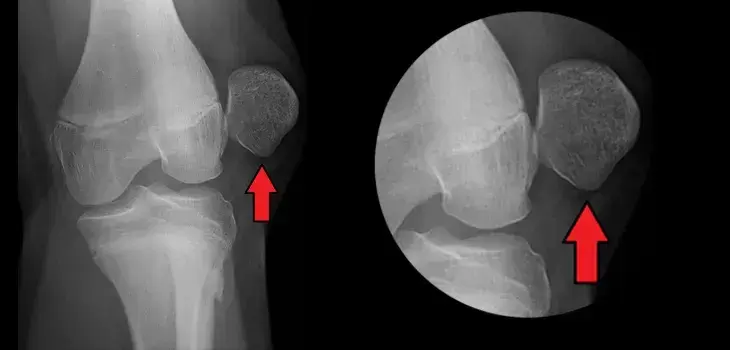

髌骨是狗狗后腿膝盖处一块形如橄榄球的小骨头,人也有类似于的组织–就是正常情况所谓的膝盖骨。髌骨可以在膝盖的滑车沟内上下左右移动,发挥作用润滑保护膝关节、维持膝关节稳定点的作用。也没了髌骨,狗狗是根本无法都正常平时走路的(下图是关节面外扭伤的X光片)。